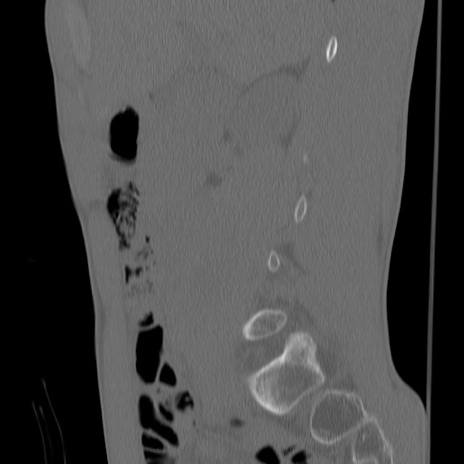

症例3 腰椎CT(矢状断像)

【症例】30歳代男性

【主訴】腰痛

【現病歴】本日旅行先で観光中に、友人と衝突し転倒し受傷。

【身体所見】麻痺なし、右下腿内側前面外側、左下腿内側に知覚鈍麻・しびれ

異常所見と診断は?

腰椎CT